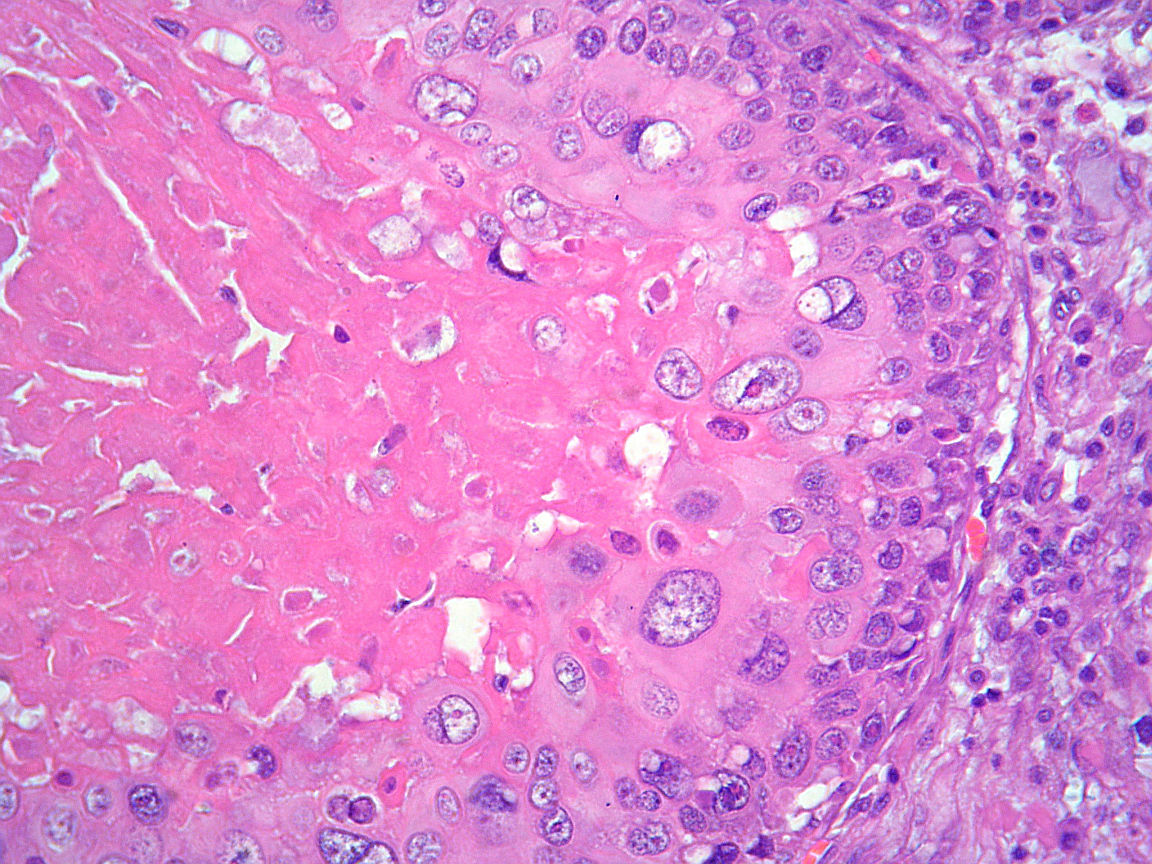

Cas dermatopatologia. Nòdul ulcerat de consistència petria al penis

Novembre 2013

Descarregar (pdf, 1.3Mb)